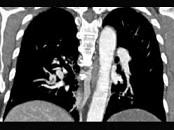

- 单项选择题男,56岁, 食管癌术后,胸痛, 呼吸困难,结合CT图像, 最可能的诊断是 ( )

A、食管癌肺转移

B、肺栓塞

C、支气管扩张

D、肺水肿

E、肺不张